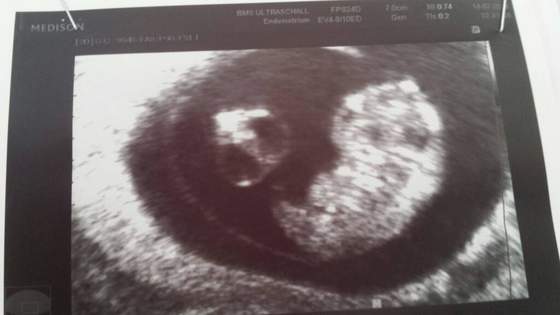

Asiu twoj dropsik taki jak moj w tamtym czasie. Ciekawe jak moj teraz urosl. Ja mam wizyte 28.

Asiu - jak fajnie :-) moja Alusia na poczatkowych usg tez miała tetno ok. 170 teraz już ma ok.140. Wiesz że podobo dziewczynki maja wyższe tętno od chłopców?:-D Fotka jest?

Po prawej "Dropsik" a po lewej 2 torbiele pepowiny.

• 1405350296208.jpg

15,7 KB · Wyświetleń: 82